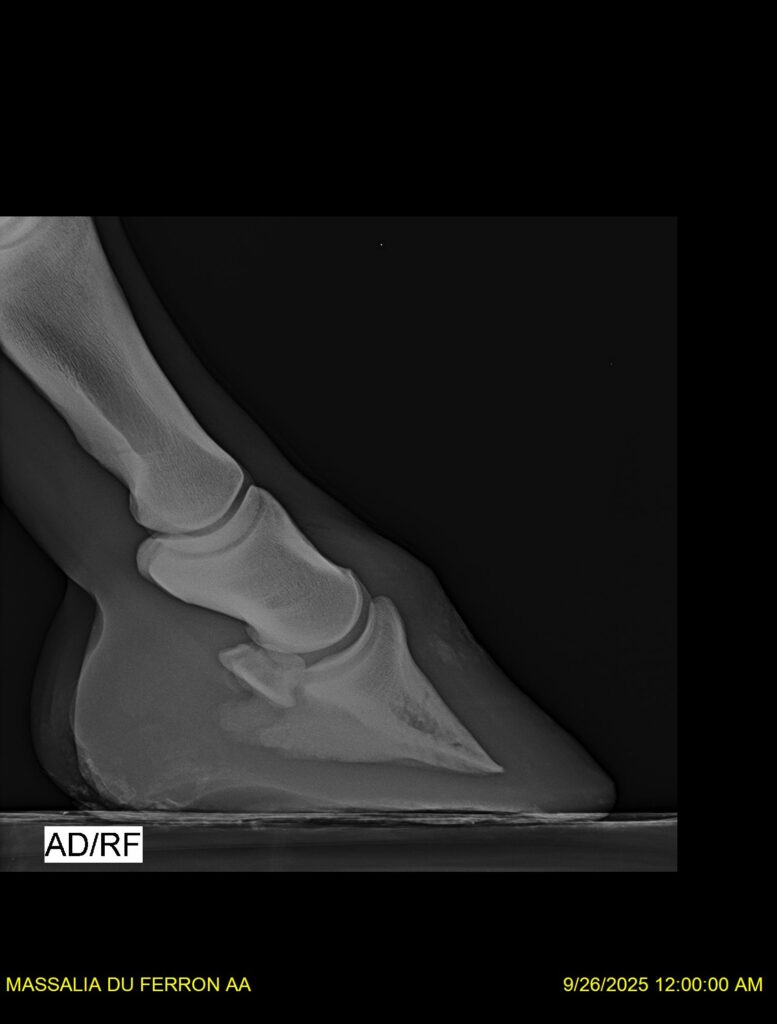

MASSALIA DU FERRON, jument qui prendra 4 ans par PRESTIGE KALONE x TRESOR DU RENOM. Un mental en or et un véritable sens de la barre ! Facile d’accès ! Bonne énergie et bons moyens. Souche moderne et très intéressante. Transport OK, maréchalerie OK, santé RAS, Bilan clichés radios OK.

RADIOS et COMPTE RENDU